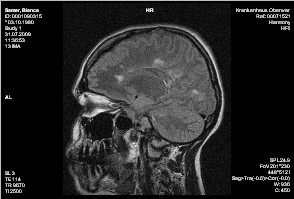

Ergebnis:

Bekannte Enc. diss.

Im Vergleich mit den mitgebrachten Bildern keine massive Zunahme der

Glialäsionen, keine kontrastmittelaufnehmenden Bezirke als Aktivitätszeichen.